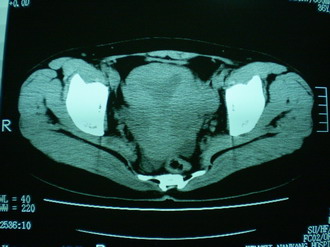

子宫增大,内可见类三角形低密度区,子宫后方可见类圆形团块状影,内部密度不均匀,可见靶样结构,结合病史考虑1子宫后方宫外孕(宫内假孕囊形成)2子宫肌瘤合并妊娠

那就支持子宫后浆膜下型肌瘤啰,有变性。盆腔及右输卵管积液?宫内积血?结合以上考虑肌瘤合并盆腔炎

子宫明显前倾,增大,宫颈增大呈分叶状。子宫直肠窝见不规则形水样低密度。(膀胱胀尿不理想)

考虑:1、宫颈部占位;

2、子宫直肠窝少量积液(盆腔炎所致)。

宫颈部肌瘤宫腔内积血,

考虑肌瘤堵塞子宫颈管导致宫腔积液。